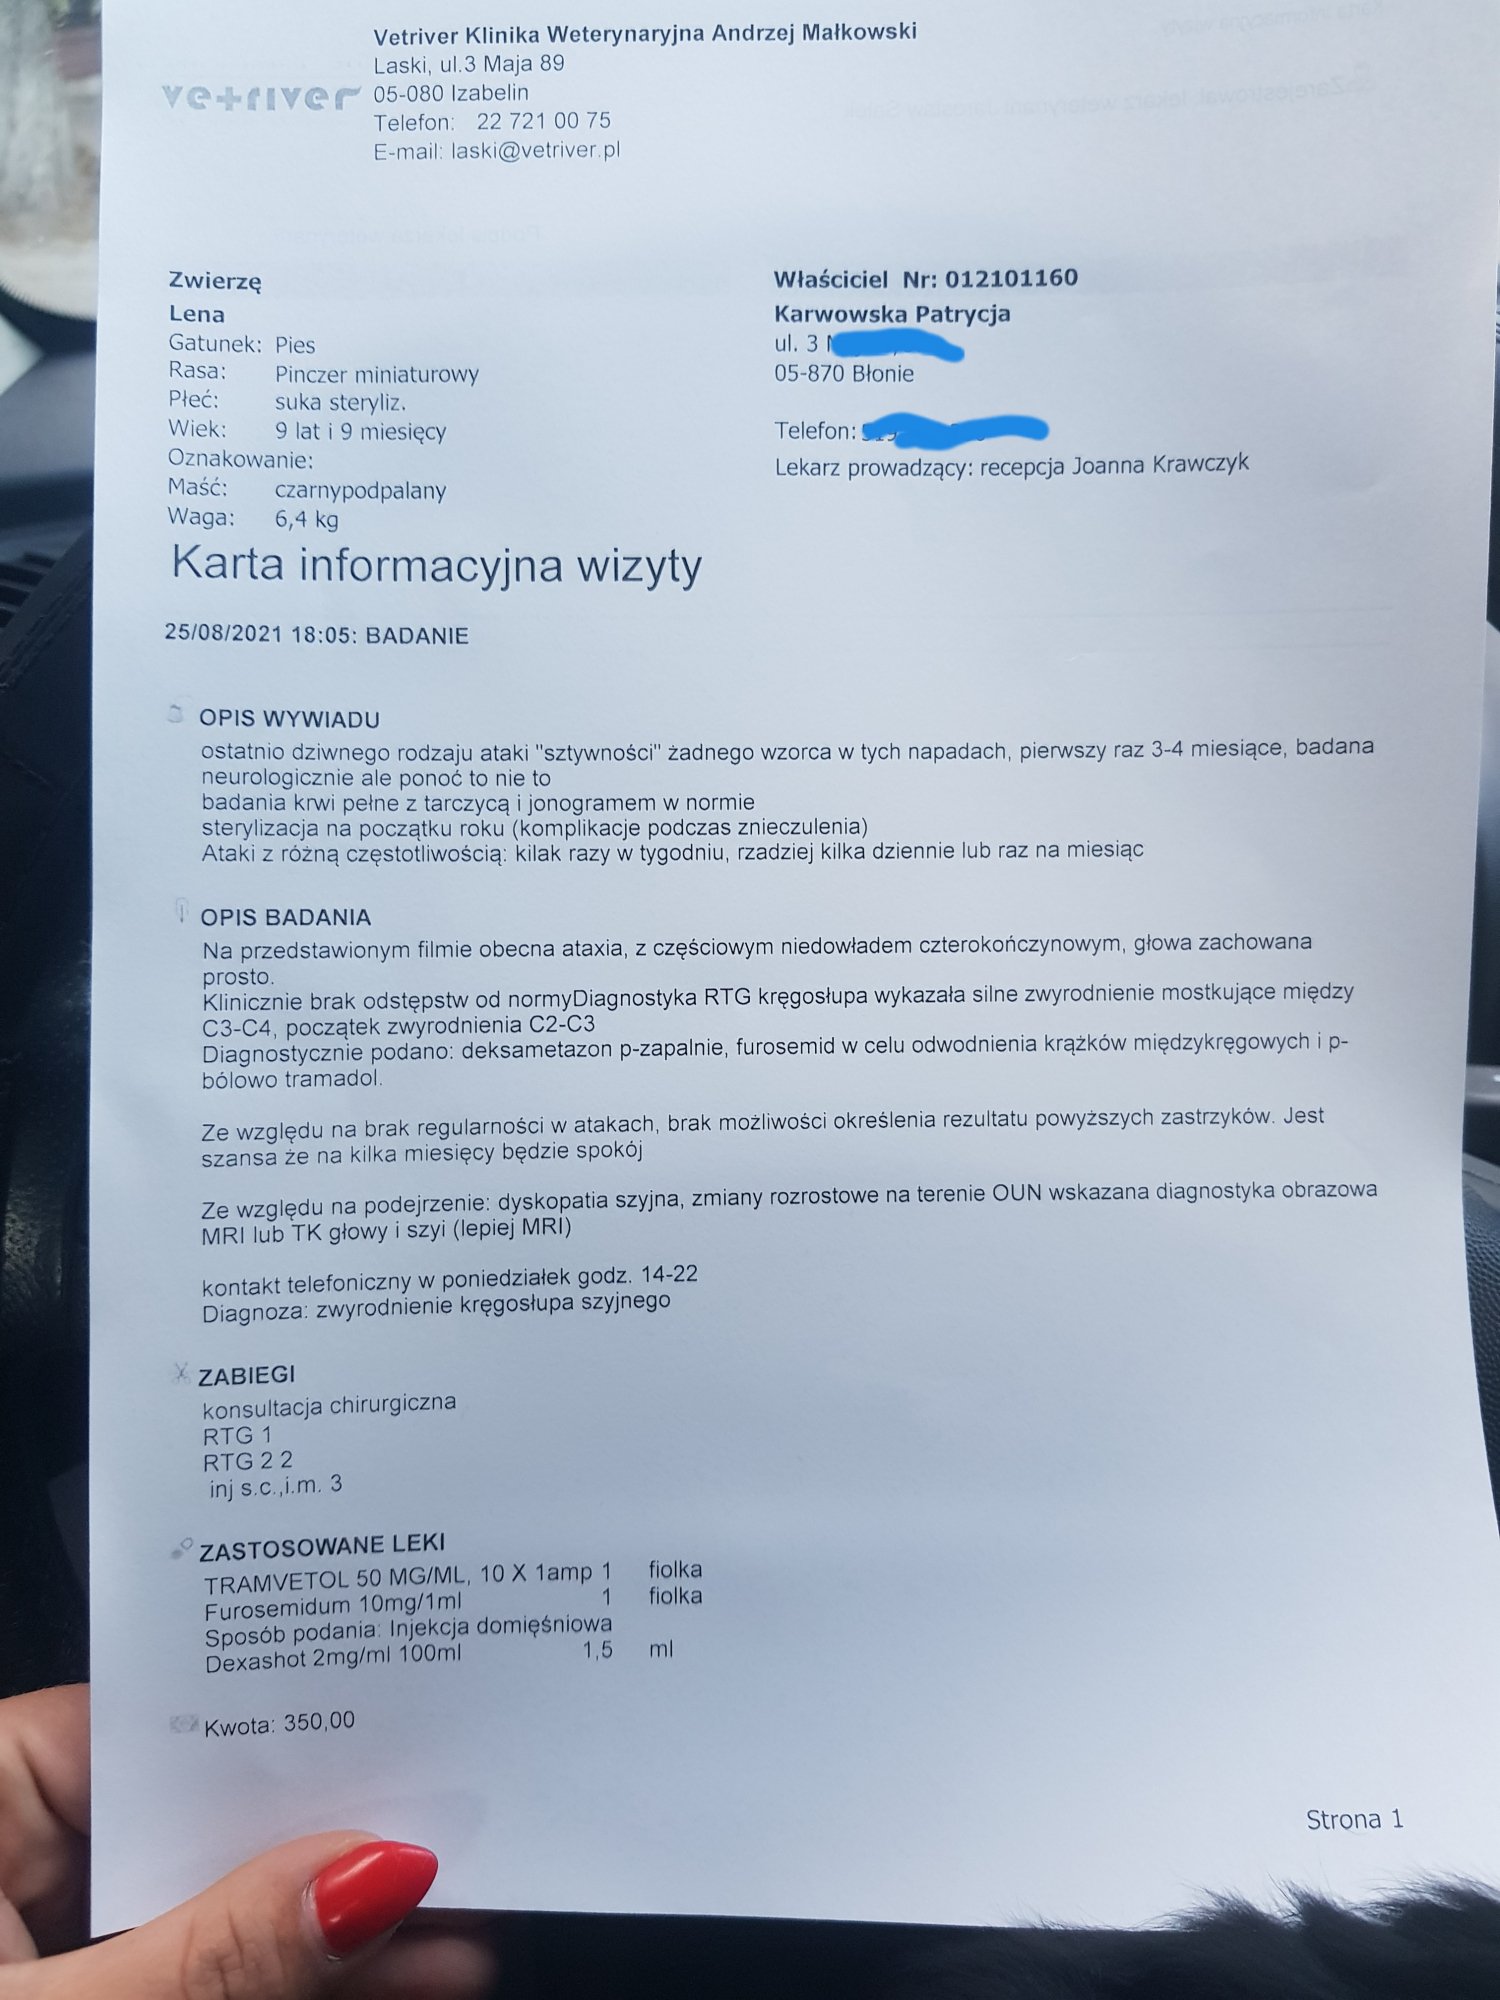

Zawsze to ja pomagam innym, ale tym razem zmuszona jestem o tą pomoc prosić. Moja ukochana psia córeczka od pewnego czasu ma ataki, które objawiają się zesztywnieniem całego ciała lub ograniczoną ruchowością i dużą trudnością w poruszaniu się. Weterynarz podejrzewał najpierw, że jest to na tle neurologicznym, została przebadana, lecz nie stwierdzono żadnych nieprawidłowości. Podejrzewał, że jest to na tle nerwowym, więc brała leki uspokajające, odstesowujace. W między czasie powtórnie wielokrotnie badana, ze względu na dalsze ataki. Badania wychodziły dobrze. W niedzielę 22 sierpnia od ok. godz. 14:00 do 22:00 (do póki nie zasnela) miała problem z poruszaniem się, każdy krok sprawiał jej trudność. W poniedziałek znów udałam się do weterynarza i pojawiły się podejrzenia, że jest to jednak na tle ortopedycznym. Dziś trafiłam do świetnego ortopedy, który wykonał szereg badań, w tym RTG - zdjęcia i opis załączone. Okazuje się, że jest duży problem zwyrodnienia. Otrzymała leki i konieczne jest wykonanie MRI oraz prawdopodobnie operacja. Nieststy to wszystko wykracza poza moje możliwości finansowe, dlatego bardzo chciała bym prosić Państwa o wsparcie. Ona jest dla mnie jak córka, bez niej nie wyobrażam sobie życia i zrobię wszystko, aby była zdrowa. Będę ogromnie wdzięczna za każdą złotówkę przekazaną na jej leczenie. Osobą zainteresowanym mogę przesłać filmiki, na których widać jak duży jest to problem i jak bardzo potrzebna jest jej pomoc.